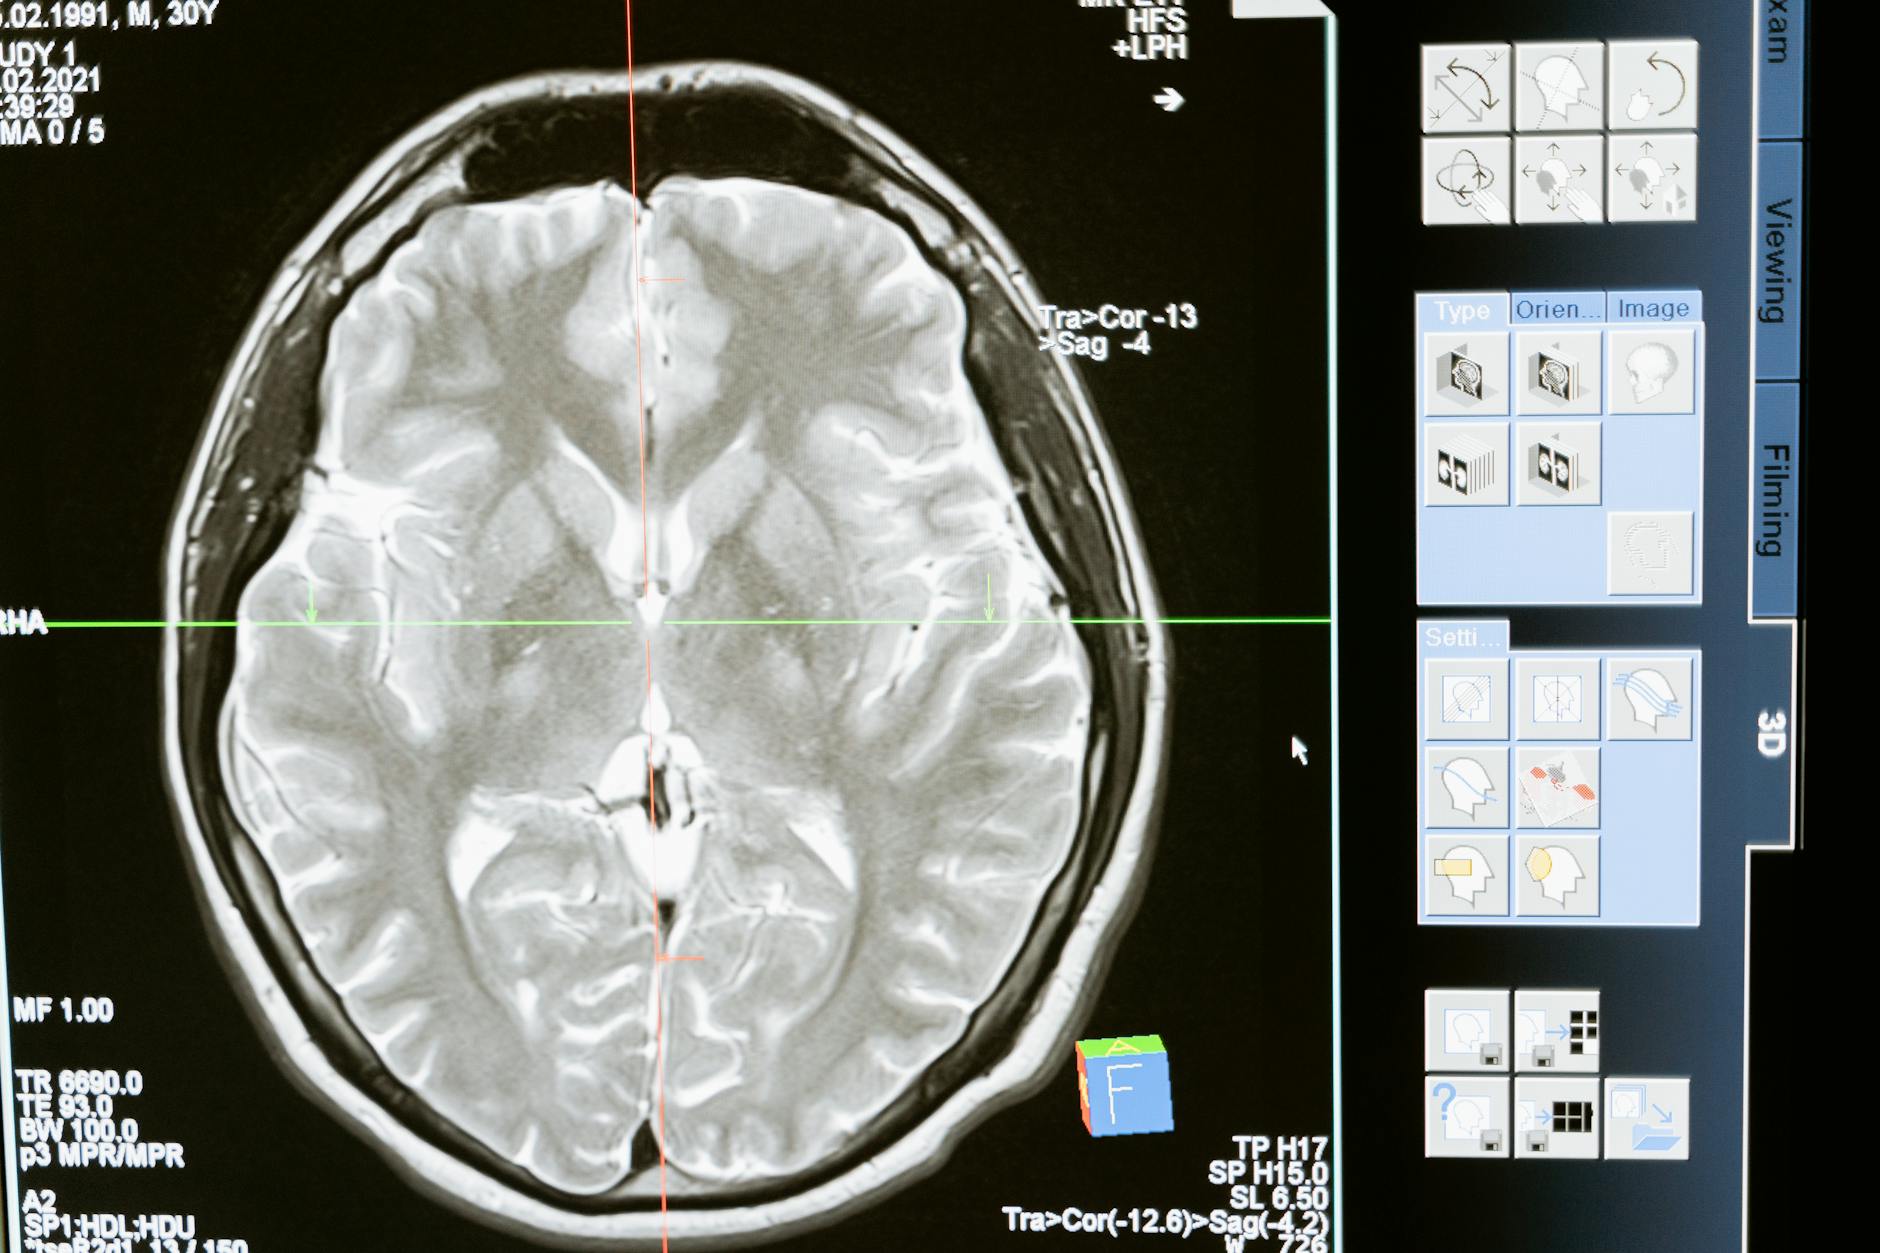

The Chemo Brain Connection — How Pancreatic Cancer Treatment Affects Cognitive Health

Chemotherapy-related cognitive impairment is not a myth or a minor inconvenience. Research published in journals such as Cancer and the Journal of Clinical Oncology has documented measurable changes in memory, executive function, processing speed, and attention in patients undergoing systemic chemotherapy. While much of this research has focused on breast cancer survivors, there is no biological reason to believe that the cognitive effects spare patients receiving FOLFIRINOX. In fact, the intensity of the regimen may increase the risk. Fluorouracil, one of the four drugs in the combination, has been specifically associated with neurotoxicity in some studies. For someone already living with mild cognitive impairment or early dementia, layering chemotherapy on top of an existing neurological vulnerability demands careful consideration. Caregivers frequently report that their loved ones seem “different” after chemotherapy — more confused, slower to find words, less able to follow conversations.

These changes can be temporary, resolving weeks to months after treatment ends, but in some patients they persist. The mechanisms are not fully understood, but likely involve a combination of direct neurotoxic effects, inflammation, oxidative stress, and disruption of neural repair processes. A specific example illustrates the stakes: a 72-year-old patient diagnosed with both localized pancreatic cancer and mild cognitive impairment might be a candidate for neoadjuvant FOLFIRINOX (given before surgery to shrink the tumor). The oncologist sees an opportunity to convert a borderline-resectable tumor into an operable one. The neurologist worries that six months of aggressive chemotherapy could accelerate cognitive decline past a tipping point. Neither specialist is wrong. This is the kind of scenario where multidisciplinary care coordination is not just ideal but essential.

Researchers are also exploring the gut microbiome’s influence on chemotherapy response and the role of the tumor’s surrounding tissue — the dense stroma that characterizes pancreatic tumors — in shielding cancer cells from treatment. For the brain health community specifically, the growing recognition of chemotherapy’s cognitive effects is driving research into neuroprotective strategies that might be administered alongside cancer treatment. Cognitive rehabilitation programs, physical exercise interventions, and even certain supplements are being studied for their potential to mitigate chemo brain. While definitive answers remain limited, the conversation has shifted from “does chemo brain exist?” to “how do we prevent or treat it?” — and that shift matters for every patient and caregiver managing the intersection of cancer and cognitive health.